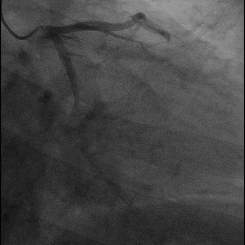

Je sais que la personne qui pose cette question a probablement été confrontée à une situation similaire, par exemple, certains patients souffrant d'une crise cardiaque aiguë qui ont été admis à l'hôpital pour de fortes douleurs thoraciques et dont les symptômes ont soudainement disparu après leur admission à l'hôpital, avant qu'ils ne puissent subir une thrombolyse ou une thérapie interventionnelle. La coronarographie a montré que les artères coronaires occluses s'ouvraient d'elles-mêmes une petite fente, ce que les cardiologues appellent souvent la thrombolyse. Ce phénomène se produit le matin, principalement parce que le corps humain possède, en plus du système de coagulation, un système fibrinolytique. Lorsque le système de coagulation du corps est activé, le système fibrinolytique est également activé, ce qui donne lieu à la scène mentionnée ci-dessus.

Ainsi, puisque le corps humain dispose d'un système fibrinolytique, pouvons-nous nous fier uniquement à ce système pour réparer les lésions des vaisseaux sanguins rétrécis ? La réponse est non, car même si vous avez beaucoup de chance, après l'occlusion des vaisseaux sanguins en raison de l'activation du système fibrinolytique, ce qui entraîne la réouverture des vaisseaux sanguins occlus du patient, il ne peut pas faire en sorte que la sténose grave des vaisseaux sanguins s'ouvre complètement, généralement pas jusqu'à l'état physiologique normal, et n'a pas la fonction physiologique normale. Ce type de sténose grave d'un vaisseau sanguin criminel est particulièrement propice à la ré-occlusion. Il est donc préférable de recourir à la chirurgie interventionnelle pour que la sténose du vaisseau sanguin devienne normale, mais aussi pour éviter le risque de ré-occlusion à un stade ultérieur.

Pour rappel, même si vous êtes dans la situation mentionnée au début de l'article, c'est-à-dire si le vaisseau sanguin occlus est recanalisé, vous devez procéder à une angiographie coronaire, voire à l'implantation de stents, car la recanalisation ne signifie pas que le vaisseau est complètement dégagé, et l'état recanalisé est souvent un état de sténose à 99 %, ce qui nécessite encore un traitement chirurgical supplémentaire. Bien entendu, il convient d'analyser la situation spécifique et de suivre le plan de traitement du médecin professionnel.

En théorie, il est possible de restaurer avec succès la reperfusion vasculaire grâce à la thrombolyse pharmacologique. Lorsque le Dr Wu était en stage dans le service de cardiologie, il a reçu un patient souffrant d'un infarctus aigu du myocarde qui lui avait été adressé par un hôpital de comté. Le patient a ressenti une douleur thoracique soudaine et s'est rendu à l'hôpital de comté local pour une consultation, et les enzymes myocardiques ainsi que les électrocardiogrammes de l'hôpital de comté local ont suggéré la présence d'un infarctus aigu du myocarde. En raison de l'absence de thérapie interventionnelle dans l'hôpital local, compte tenu de l'heure d'apparition de l'infarctus et du faible risque de saignement, il a été demandé au patient et à sa famille de donner leur accord pour une thérapie thrombolytique, et le patient a été transféré dans notre hôpital pour une intervention thrombolytique supplémentaire après la thérapie thrombolytique. Le patient était prêt pour la pose d'un stent, mais après la coronarographie, l'artère coronaire sténosée a été recanalisée, avec seulement 20 à 30 % de sténose, de sorte qu'il n'a pas été nécessaire d'implanter un stent.

Pour l'infarctus aigu, si les conditions sont réunies, le premier choix de traitement est l'ICP directe (diagnostic interventionnel coronarien), c'est-à-dire la chirurgie interventionnelle pour recanaliser les vaisseaux sanguins rétrécis, l'implantation de stents coronariens, qui est actuellement le meilleur moyen de restaurer la reperfusion des vaisseaux sanguins ; pour les patients qui ne réunissent pas les conditions pour effectuer une ICP et dont le délai d'apparition de la maladie est inférieur à 12 heures, l'évaluation du risque d'hémorragie peut être choisie après la thrombolyse médicamenteuse. Après la thrombolyse pharmacologique, il est toujours nécessaire de transférer le patient dans un hôpital qui dispose des conditions nécessaires pour effectuer une ICP afin de poursuivre la thrombolyse et ensuite l'ICP, tout comme dans l'exemple cité précédemment, si le vaisseau sanguin est recanalisé, il n'est pas nécessaire d'implanter un stent, mais si le vaisseau sanguin est toujours sténosé à un degré supérieur à 70 %, un stent devra être implanté !

Ce que nous pouvons dissoudre, c'est un thrombus nouvellement formé, mais pour une sténose qui existe depuis longtemps, les médicaments ne sont pas en mesure de la dissoudre. La sténose est la formation d'une plaque après l'athérosclérose, qui obstrue ensuite la lumière pour former ce que l'on appelle une sténose. Après la formation de la plaque, celle-ci ne peut pas être dissoute par les médicaments. Le thrombus aigu formé après la rupture de la plaque peut être dissous, mais la partie du thrombus aigu qui peut être dissoute ne comprend pas la sténose résiduelle d'origine. L'importance de la sténose résiduelle est l'un des principaux facteurs déterminant la mise en place ou non d'un stent après une thrombolyse.